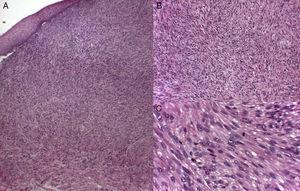

Desde el punto de vista histopatológico, se han descrito dos patrones arquitecturales: el patrón nodular, caracterizado por una mayor celularidad, atipia y figuras de mitosis, y el patrón difuso, menos celular y con menor carga mitótica. En ocasiones, no existe una atipia celular evidente, por lo que el diagnóstico histológico debe apoyarse en la arquitectura global de la lesión (patrón infiltrativo, celularidad aumentada). La toma correcta de muestras para estudio histopatológico tiene especial relevancia, siendo de elección las biopsias incisionales que alcancen la hipodermis. El estudio inmunohistoquímico es una herramienta fundamental para el adecuado diagnóstico diferencial de las neoplasias de células fusiformes y su procedencia11 (fig. 2).

Infiltración difusa y mal delimitada de fascículos entrelazados de fibras musculares lisas, compuestas por células fusiformes, de núcleo alargado y extremos romos («en forma de cigarro puro») con marcado pleomorfismo y un citoplasma eosinófilo. (Tinción de hematoxilina-eosina: A. X10 B. X20C. X40).